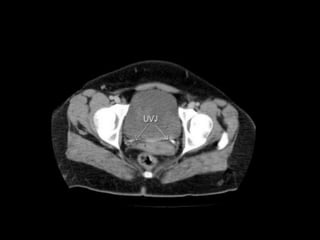

Urinary Bladder:

 The urinary bladder is covered superiorly by peritoneum.

 The body is a hollow muscular cavity.

 The neck is continuous with the urethra.

 The trigone is a smooth triangular area of mucosa located

internally at the base of the bladder.

 The base of the triangle is superior and bounded by the two

openings of the ureters.

 The apex of the trigone points inferiorly and is the opening for

the urethra.

Ureters : arefibro-muscular tubes that connect the kidneys to the urinary bladder in the pelvis. Urinary Bladder:  The urinary bladder is covered superiorly by peritoneum.  The body is a hollow muscular cavity.  The neck is continuous with the urethra.  The trigone is a smooth triangular area of mucosa located internally at the base of the bladder.  The base of the triangle is superior and bounded by the two openings of the ureters.  The apex of the trigone points inferiorly and is the opening for the urethra. 3/22/2024 ABDOMEN PRESENTATION BY SUDIL 74